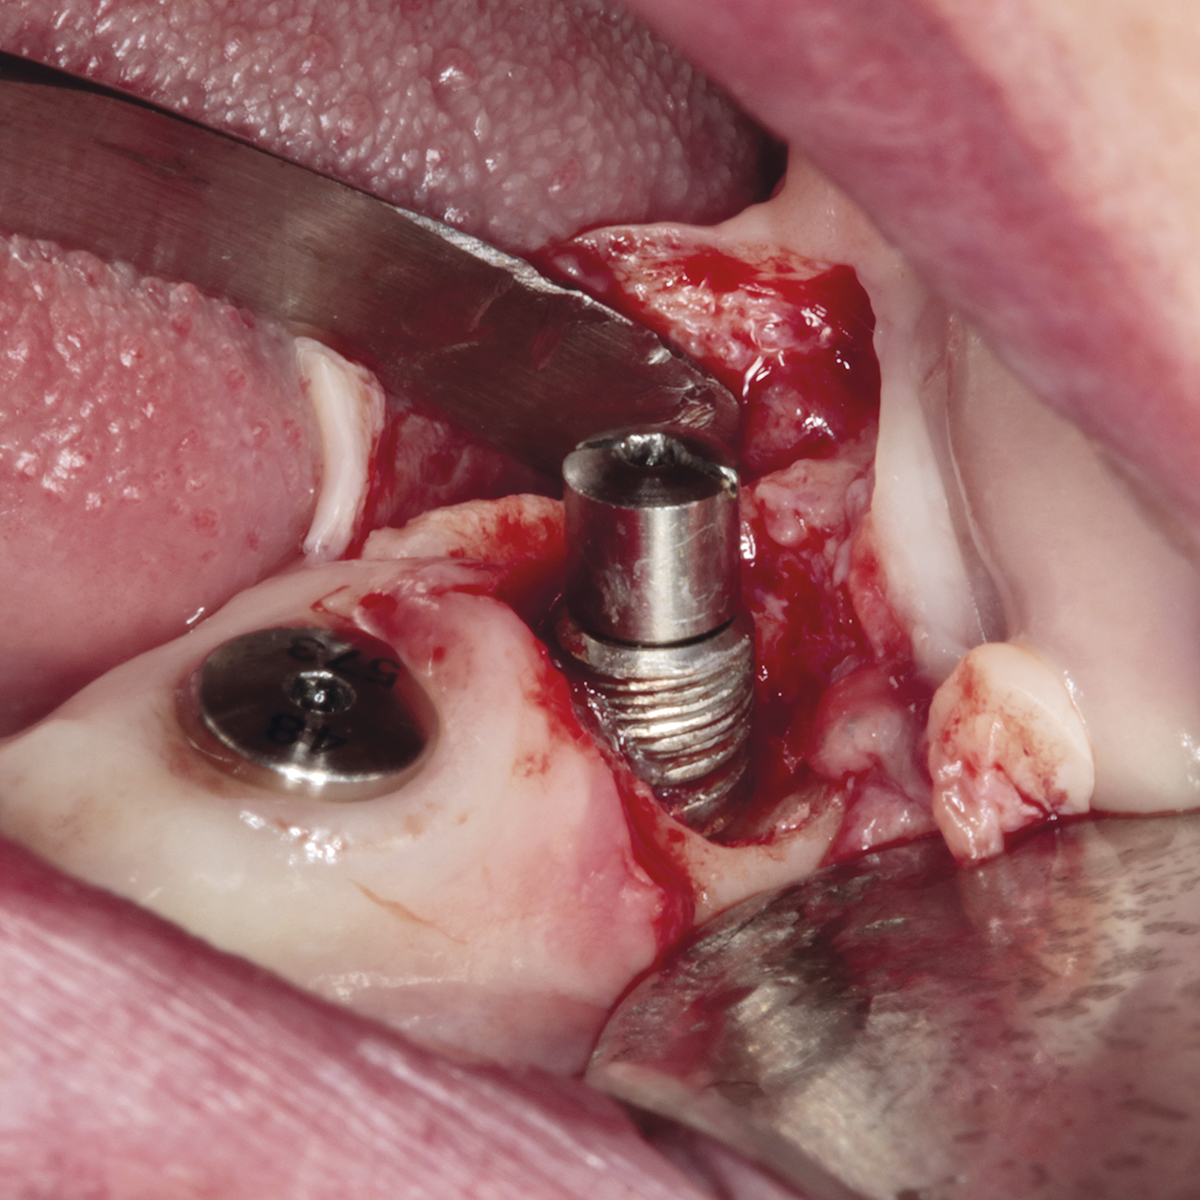

- Implantes dentales